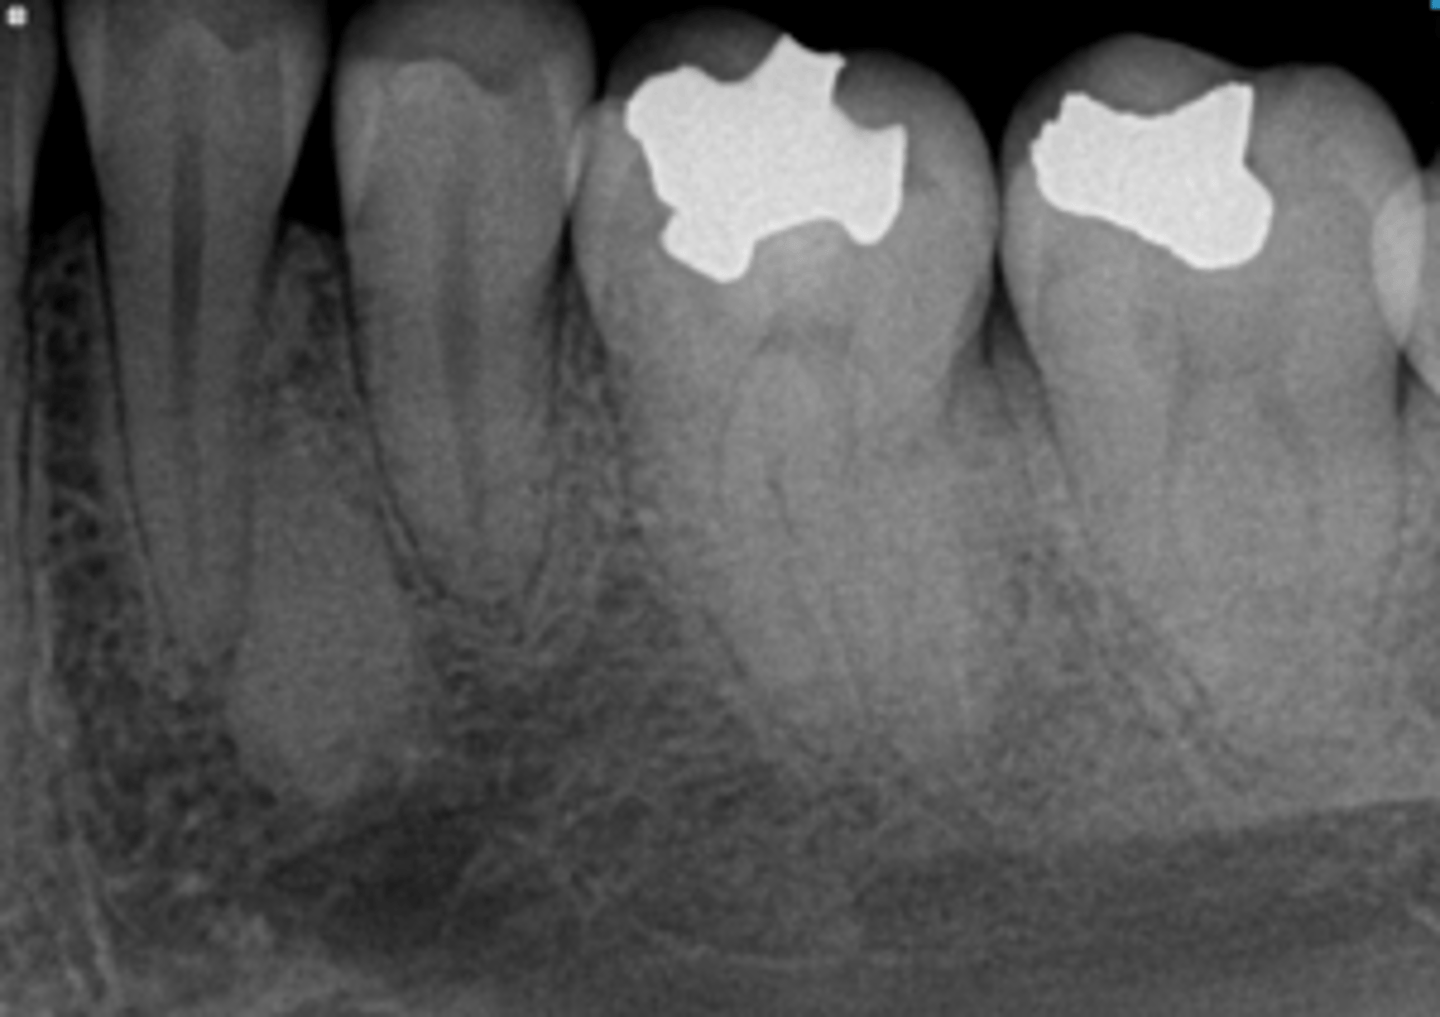

how would you describe this lesion? (not the giant cavity btw)

A. defined, corticated, periapical radiolucency causing loss of lamina dura and PDL space on #6-7

B. defined, non-corticated, periapical radiolucency causing loss of lamina dura and PDL space on #6-7

C. ill-defined, circular radiolucency located above tooth #7

D. well-defined, corticated, radiopacity

- Also note epicenter located above apex # 7 which has large dental caries.

What category would this lesion be part of?

Inflammation/benign

all of the following could be a differential diagnosis for the following lesion EXCEPT?

A. radicular cyst

B. Periapical granuloma

C. apical rarefying osteitis

D. renal osteodystrophy

what category would this lesion be classified into?

inflammatory/benign cystic